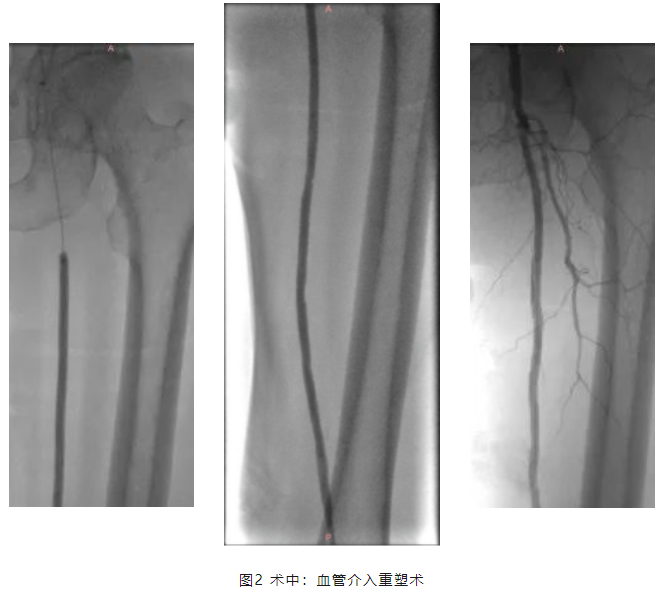

? ? ? ?手術(shù)由介入科主任陳俊偉主刀,通過(guò)下肢動(dòng)脈介入血管重塑術(shù),一步到位的擴(kuò)張狹窄的下肢動(dòng)脈,再予以藥涂球囊貼敷,進(jìn)一步提高動(dòng)脈的長(zhǎng)期通暢率,手術(shù)過(guò)程順利。